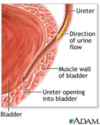

The ureter traverses the wall of the bladder in an……………… direction. Therefore, both pressure from a filling bladder and bladder contraction during micturition (urinating) inhibit reflux of urine into the ureter.

oblique